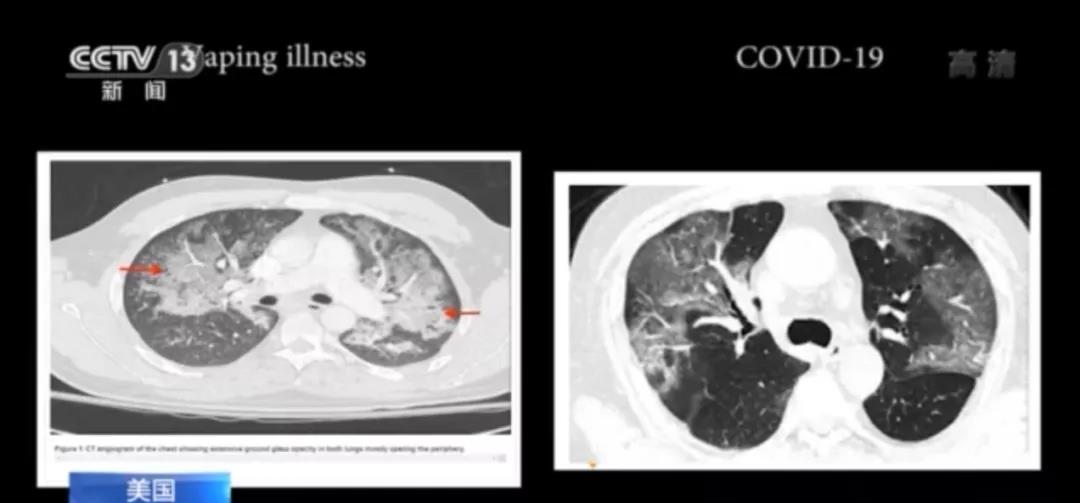

2019年7月,美國威斯康星州暴發了神秘電子煙肺炎。隨後,這種疾病席捲美國多州。 一位醫生稱,入院治療的病人大多呼吸困難、咳嗽、高燒,且大多數有流感的症狀。其病症與新冠肺炎症狀幾乎沒有差別,且致病原因未知。

時間上的巧合和肺部CT的相似讓人們不禁聯想到所謂「電子煙肺炎」和新冠肺炎之間的關係。有網友稱,「如果說新冠病毒是實驗室洩漏的,我懷疑這就是德特里克堡乾的」。